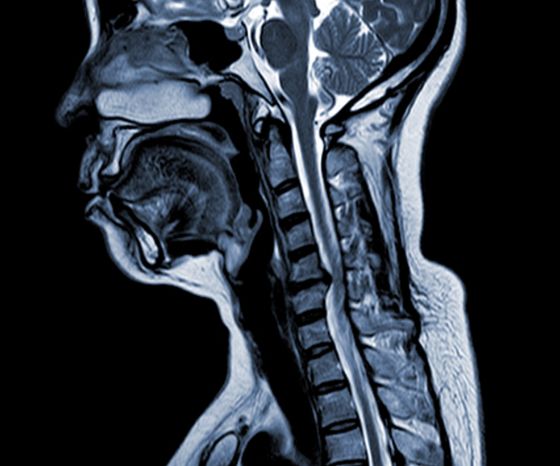

Cervikální spondylotická myelopatie (CSM)

• Mezi hlavní faktory patří degenerace disku, tvorba subperiostální kosti, osifikace zadního podélného vazu a hypertrofie ligamentum flavum, což vede ke kompresi a zúžení páteřního kanálu.